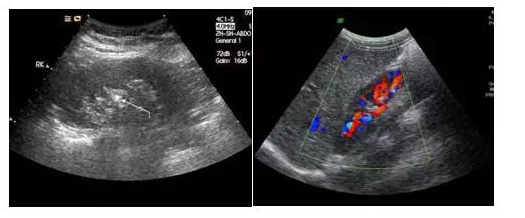

它們的區(qū)別是黑白超用灰度調(diào)制顯示聲束掃描人體切面的聲像圖;彩超則是在黑白超的基礎(chǔ)上,增加了血流信號(hào)的處理,一般用紅、藍(lán)、綠三種基本顏色,呈現(xiàn)出檢查區(qū)域的血管分布、血流方向、血流速度等。

黑白超                            彩超